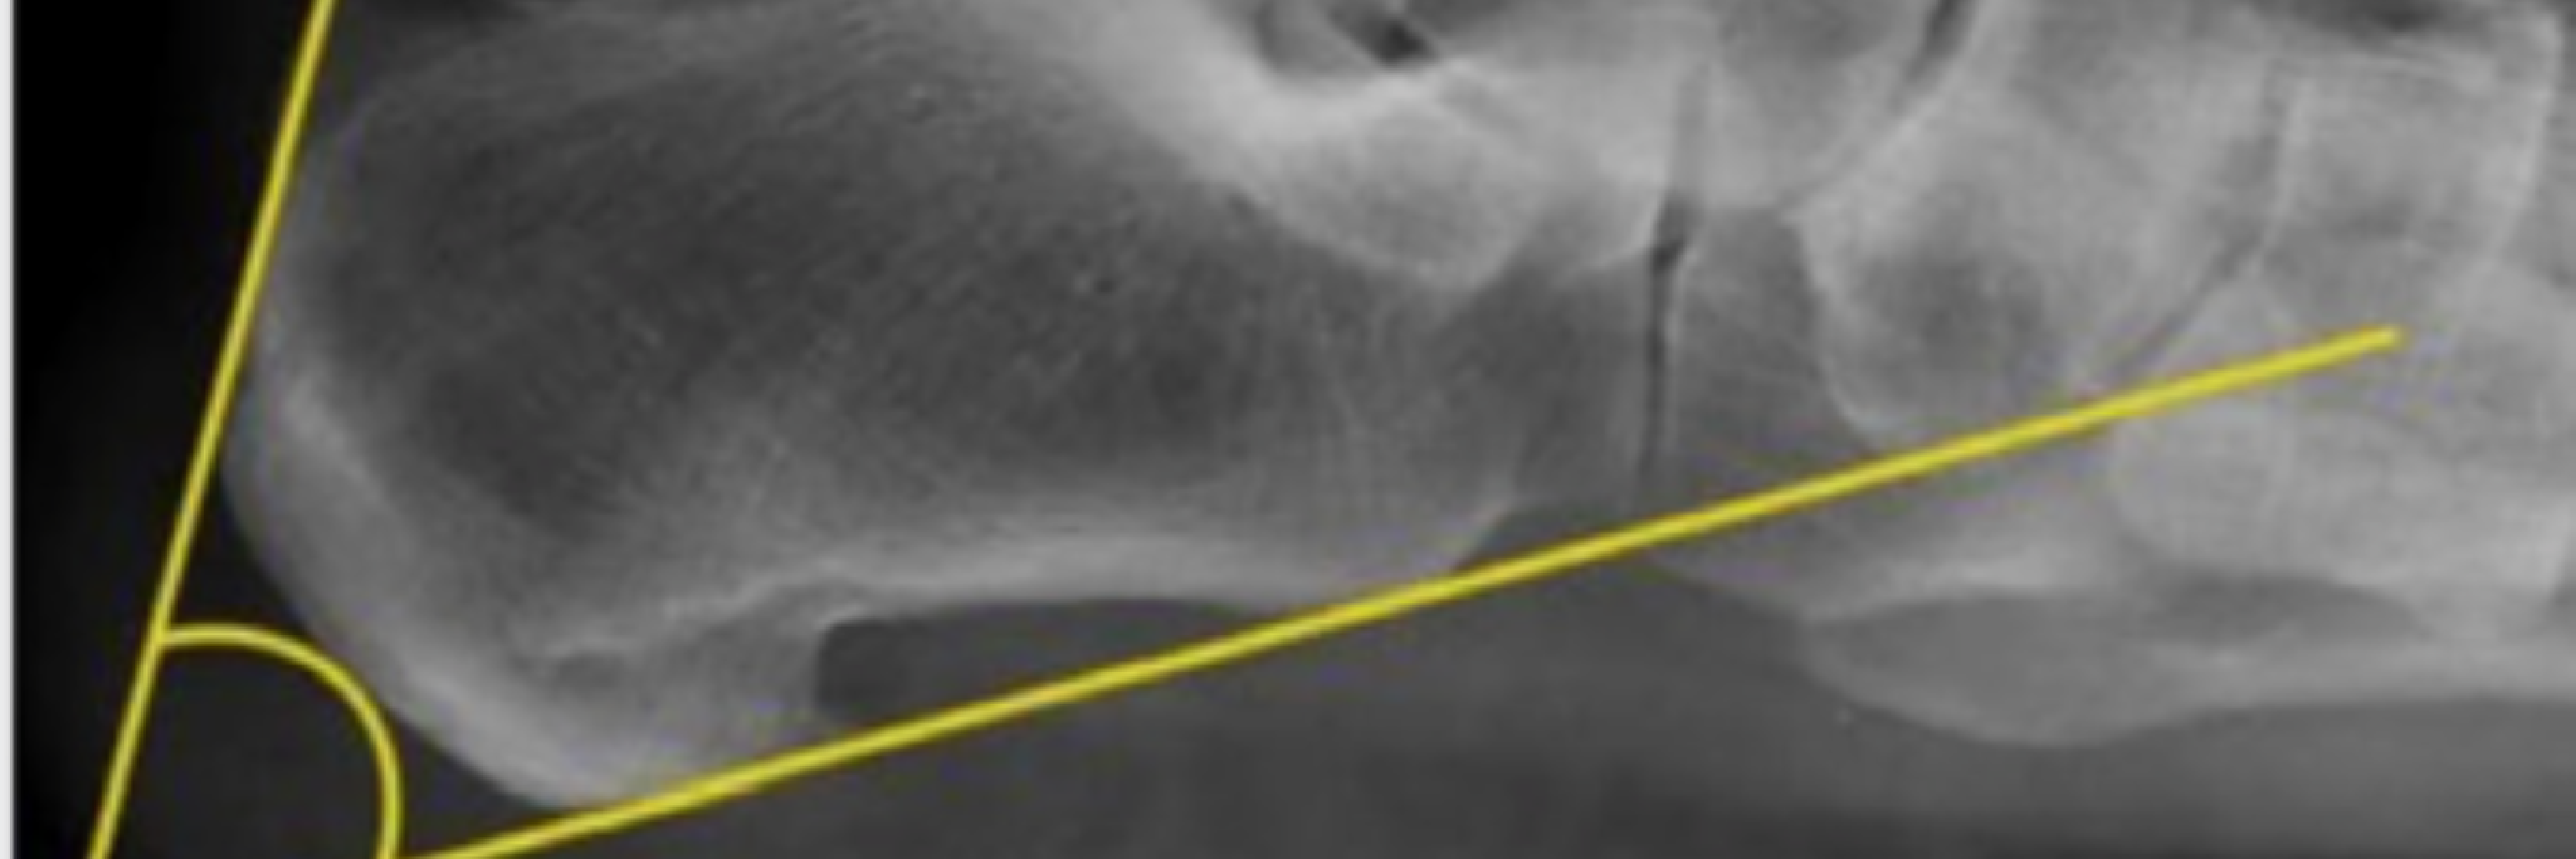

Objective: The purpose of this study was to analyze the sagittal plane variations of intraarticular ...

Objective: To compare the radiological parameters of the normal population with the patients with ...

While the Achilles tendon (AT) is the strongest and thickest tendon in the human body, it is also th ...